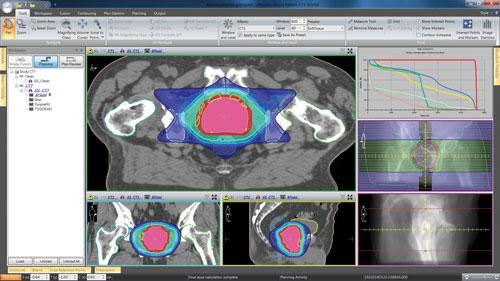

Patients in the study were randomly assigned to receive either conventional RT, consisting of 73.8 Gy in 41 daily treatments delivered over 8.2 weeks, or hypofractionated RT, consisting of 70 Gy in 28 daily treatments delivered over 5.6 weeks. A total of 962 patients reported HRQoL data, including 478 men from the C group and 448 men from the H group. The median patient age was 67 years, and baseline characteristics were similar between the treatment groups.

HRQoL was assessed with the Expanded Prostate Index Composite (EPIC), a comprehensive instrument designed to evaluate patient-reported side effects after prostate cancer treatment. The questionnaire measured side effects in each of EPIC’s four domains — bowel, urinary, sexual and hormonal. EPIC assesses prostate cancer-specific HRQoL on a Likert scale with responses transformed to 0-100, where higher scores indicate a better HRQoL. Participant feedback was collected at baseline, six months after treatment began and one year post-treatment, with change scores compared between the C and H groups. A Wilcoxon test was used to assess differences.